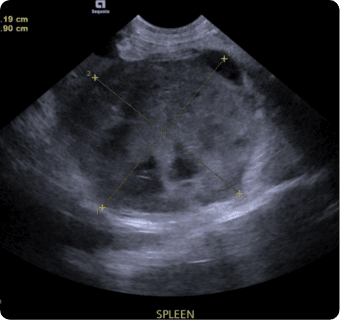

일산시티동물의료센터는 지멘스에서 개발한 고성능 프리미엄 초음파 장비인

Siemens Sequoia를 활용하여 심장, 복부 장기, 림프절 등의 구조물을 선명하게 구현하고,

미세한 해부학적 구조까지 정밀하게 확인할 수 있습니다.

또한 급성 췌장염, 급성 신부전, 자궁축농증, 방광염, 요로결석, 소화기 이물,

비장종양 등의 질환을 진단하고, 환자의 상태를 평가하는 데에도 활용됩니다.